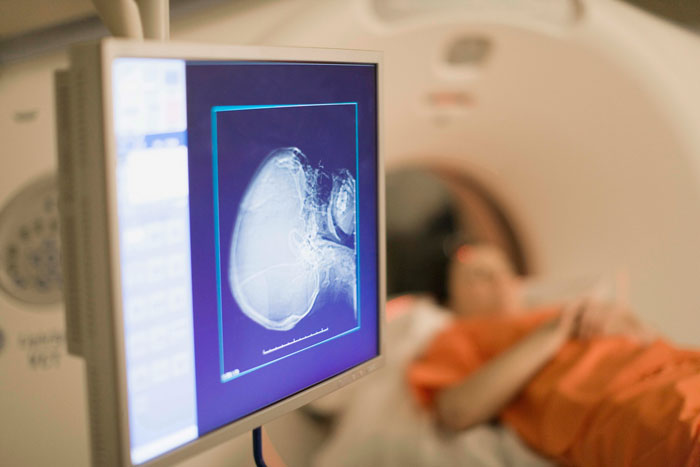

Lee explains that the most certain way to know is through diagnosis, which usually involves a CT scan and then an MRI.

The only way to get a sure diagnosis is with an MRI

Be that as it may, MRIs help with diagnosis with treatment options thereafter being available.

“So if there is a referral to MRI, the diagnosis is pretty simple and straightforward. To diagnose it works,” Lee observed.